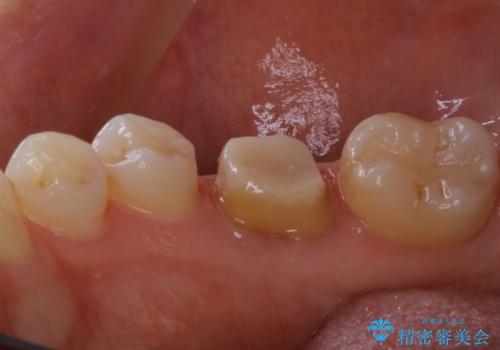

- 歯が欠けてしまったと来院された方です。

メタルインレーが一部欠けており、その下には大きな虫歯ができていました。

再精密根管治療もご提案しましたがご希望されなかったため、今回は土台と被せ物のみ治療介入しました。